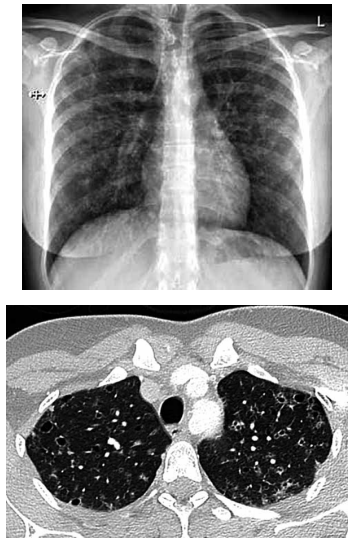

Mulher de 26 anos tem história de tosse crônica com secreção amarelada associada a dispneia ao subir escadas rapidamente. Ela fuma trinta cigarros por dia, com histórico de 13 anos-maço. Os testes de função pulmonar revelam (% do previsto): VEF1: 94%; capacidade vital forçada: 94%; capacidade pulmonar total: 107%; capacidade pulmonar de difusão de monóxido de carbono (TLCO): 57%. A radiografia e tomografia realizadas são mostradas a seguir:

Enunciado 4918945-1

O exame que mais provavelmente deve confirmar a principal hipótese diagnóstica é